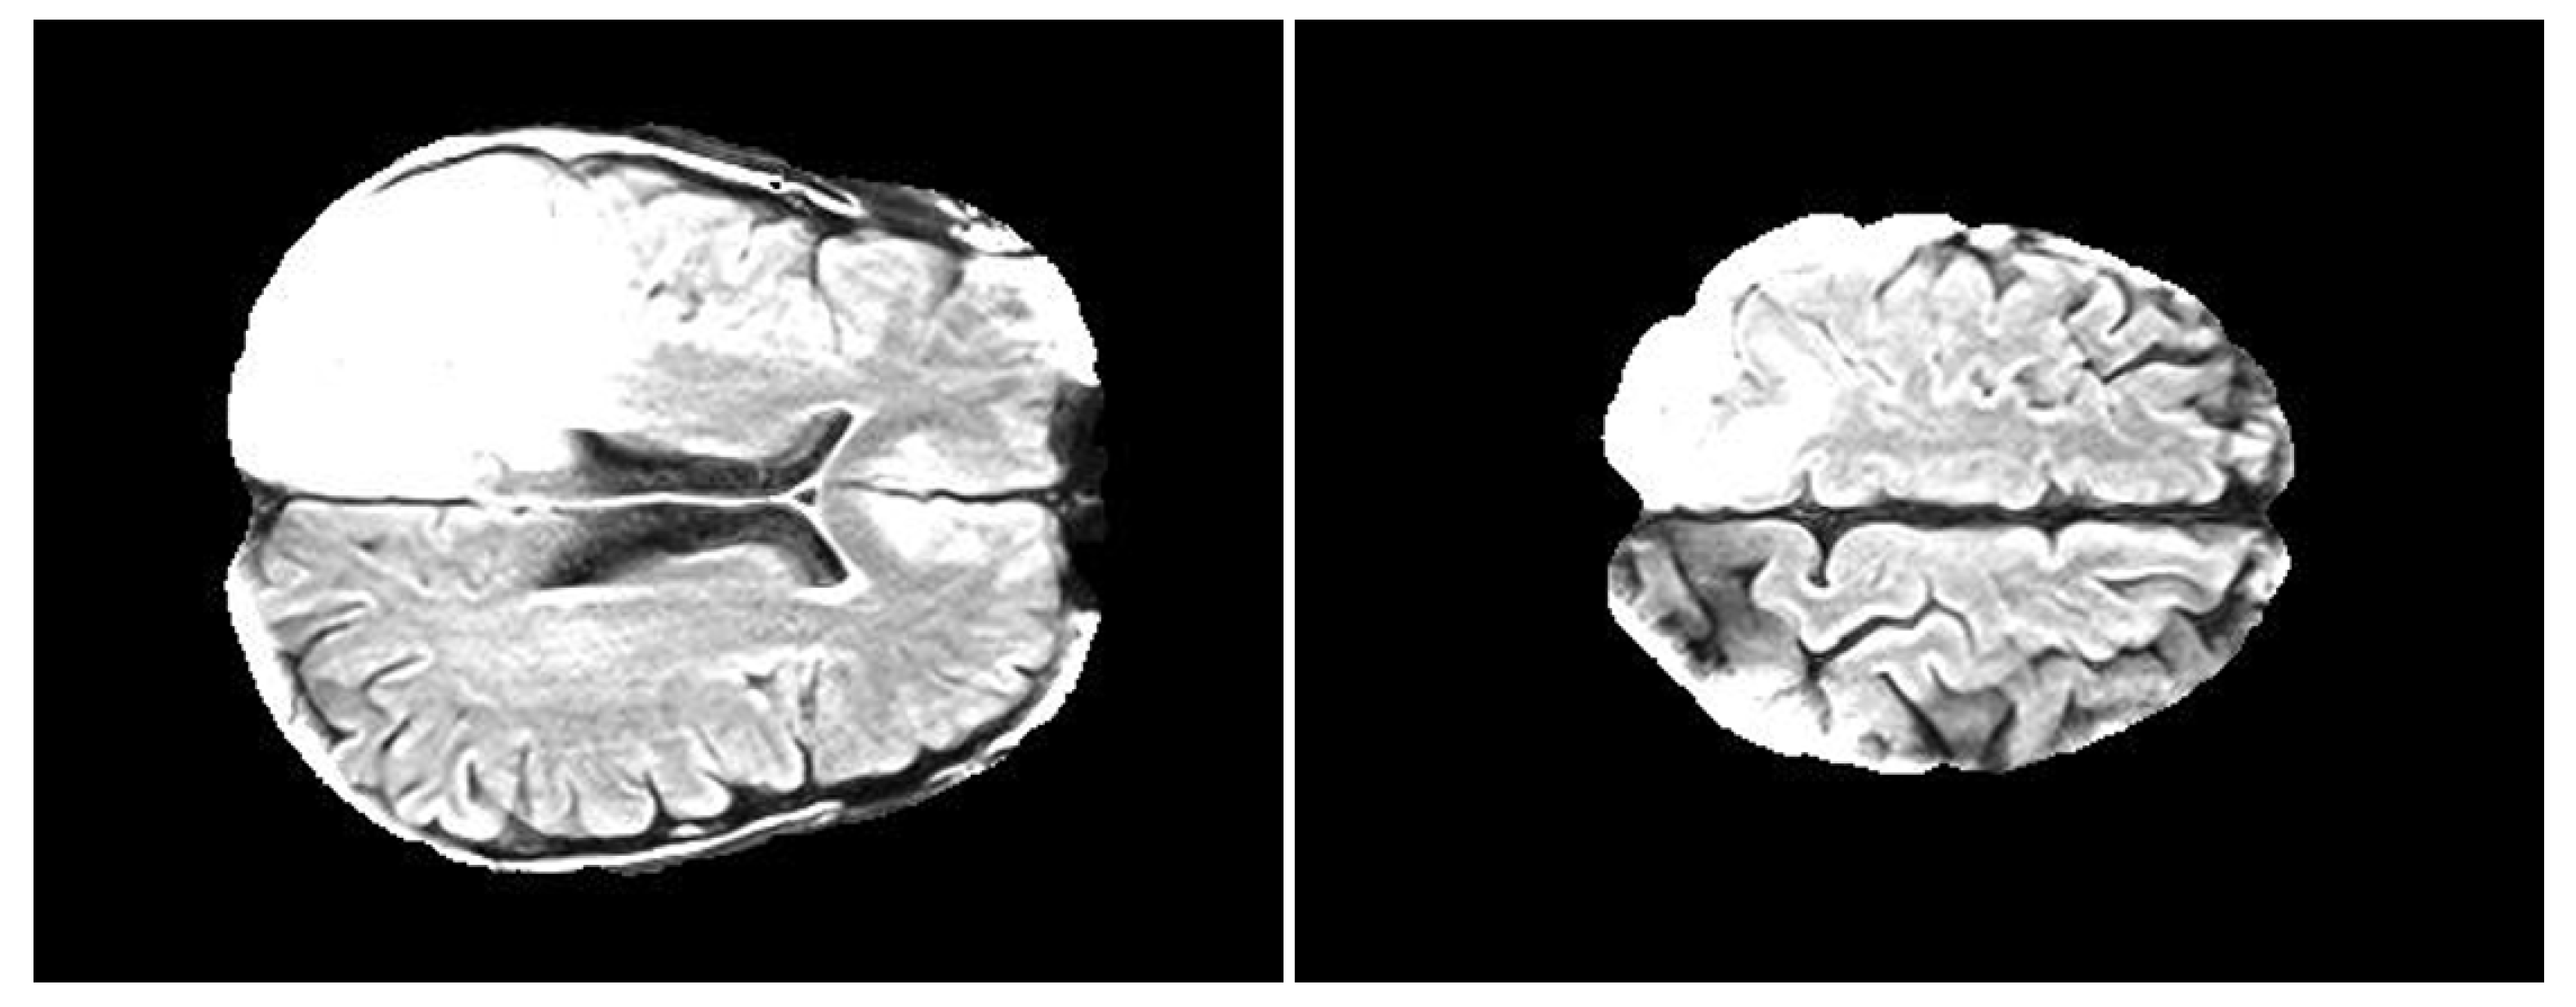

2.3. FLAIR Preprocessing

- FLAIRs were optimized by removing fat tissues and by performing skull stripping. The preprocessing steps, namely the removal of fat tissues and skull stripping, were performed by using the deep-learning algorithm described in Reference [52] (https://github.com/JanaLipkova/s3).

- From both preprocessed “pre” and “post” FLAIRs (i.e., after skull stripping) extract all the slices containing the tumor according to the corresponding ROIs.